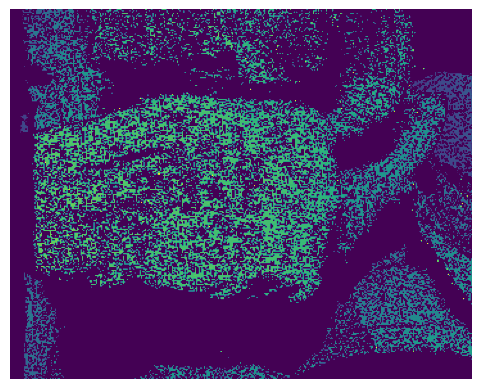

Figure 4: This figure contains an example output from the structured light network applied on the medical dataset. The top row contains the ground truth images and the bottom row shows the predictions.

Virtual dataset validation: The results on the virtual dataset, at the first two rows of Table 1, show that it is possible to achieve good reconstruction using the proposed approach. Virtual Seg denotes the metrics for the virtual object and the podium, segmented using masks provided by VisionBlender. Comparison between both approaches shows that comparable performance can be expected. For the virtual data, the training provided to the disparity network is higher quality than the structured light, as the disparity is extracted directly from the simulation environment. We hypothesise that this is the primary cause of the performance difference between the two implementations. The training/test split was 80/20, at the object level.

Medical dataset validation: Taking the networks trained on the virtual scenes, fine tuning on the medical dataset, shown in Fig. 4, is performed to reveal the benefit of using structured light when the size of the datasets are limited. The training data for the structured light was 9 times larger than for the direct disparity network because 9 patterns were collected for every depth map. The results are shown in the bottom row of Table 1. The accuracy recorded from the proposed method was twice as high as the direct regression approach. This verifies that having the larger volume of data for structured light training, when the datasets are small, improves the accuracy of the estimated disparity because of the increased complexity of the task and the increased number of training samples. The training/test split was 80/20, at the keyframe level.